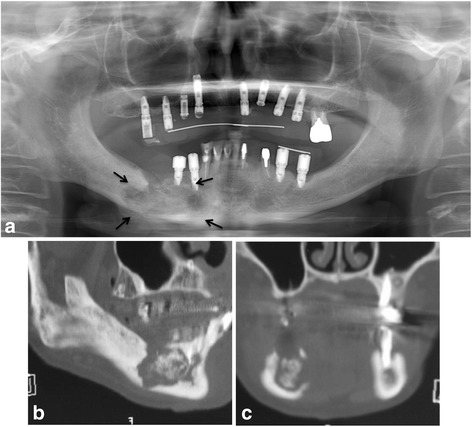

Fig. 2.

a Panoramic radiograph showing marked alveolar bone resorption surrounding the dental implant replacing the right mandibular first molar (arrow). b Sagittal CT view. c Coronal CT view

In September 2011, the patient was referred to our clinic because her symptoms were getting worse. Clinical examination revealed an intraoral fistula on the lingual side of the dental implant replacing the right mandibular first molar, associated with mucosal inflammation and a purulent discharge (Fig. 1a, b). She also had hypoesthesia of the right lower lip. The patient underwent panoramic radiography (Fig. 2a) and computed tomography (CT), which showed bone resorption around the dental implant in the right mandibular first molar area and severe peri-implantitis in the right mandibular molar region. There was no obvious sequestrum separation (Fig. 2b, c). Under a clinical diagnosis of perimandibular inflammation and peri-implantitis, conservative treatment consisting of local irrigation and use of antibiotics was implemented. Meropenem hydrate was given initially, then changed to ampicillin/sulbactam. The inflammatory state improved, and when the symptoms subsided, treatment with clarithromycin was continued. Debridement and removal of the dental implant in the right mandibular first molar area was performed under local anesthesia. Irrigation of the site was continued as part of the treatment regimen.